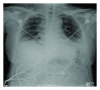

We describe a 51-year-old woman who was admitted to hospital because of cough and expectoration accompanied with general fatigue and progressive dyspnea. Chest HRCT scan showed areas of ground glass attenuation, consolidation, and traction bronchiectasis in bilateral bases of lungs. BAL fluid test and transbronchial lung biopsy failed to offer insightful evidence for diagnosis. She was clinically diagnosed with acute interstitial pneumonia (AIP). Treatment with mechanical ventilation and intravenous application of methylprednisolone (80 mg/day) showed poor clinical response and thus was followed by steroid pulse therapy (500 mg/day, 3 days). However, she died of respiratory dysfunction eventually. Autopsy showed diffuse alveolar damage associated with hyaline membrane formation, pulmonary interstitial, immature collagen edema, and focal type II pneumocyte hyperplasia.